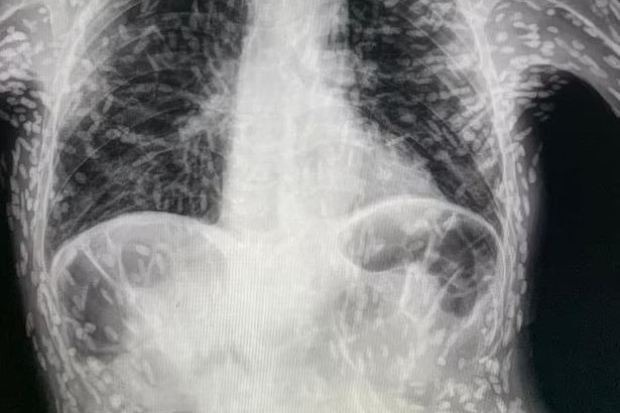

أشعة سينية تكشف حالة صادمة لمريض مصاب بالديدان الشريطية

أصيب رجل بسعال شديد وعند ذهابه إلى المستشفى، فوجئ الأطباء بصور الأشعة السينية؛ حيث وجدوا أن الديدان الشريطية تملأ أنسجة وعضلات الرجل، وذلك وفقًا لذا صن البريطانية.

كشفت الأشعة السينية، التي شاركها طبيب على تويتر، عن مئات النقاط مضيئة التي تشير إلى بقايا متكلسة لطفيلي، وتحدث هذه الحالة المسماة داء الكيسات المذنبة، عندما تدخل يرقات أحد أنواع الدودة الشريطية؛ التي تعيش عادةً في الأمعاء، إلى أنسجة مثل العضلات أو الدماغ.